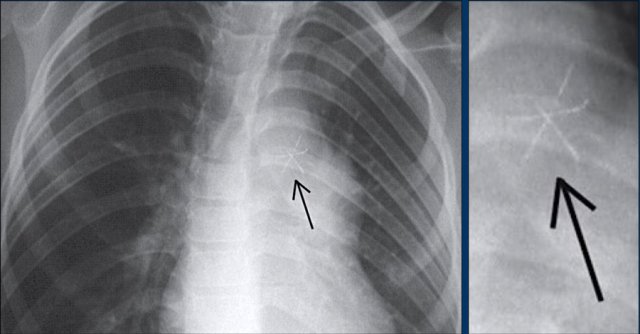

Lead fracture

Obvious fracture of one of the leads.

Subtle lead fracture in malfunctioning pacemaker.

Extremely subtle fracture line (arrow).